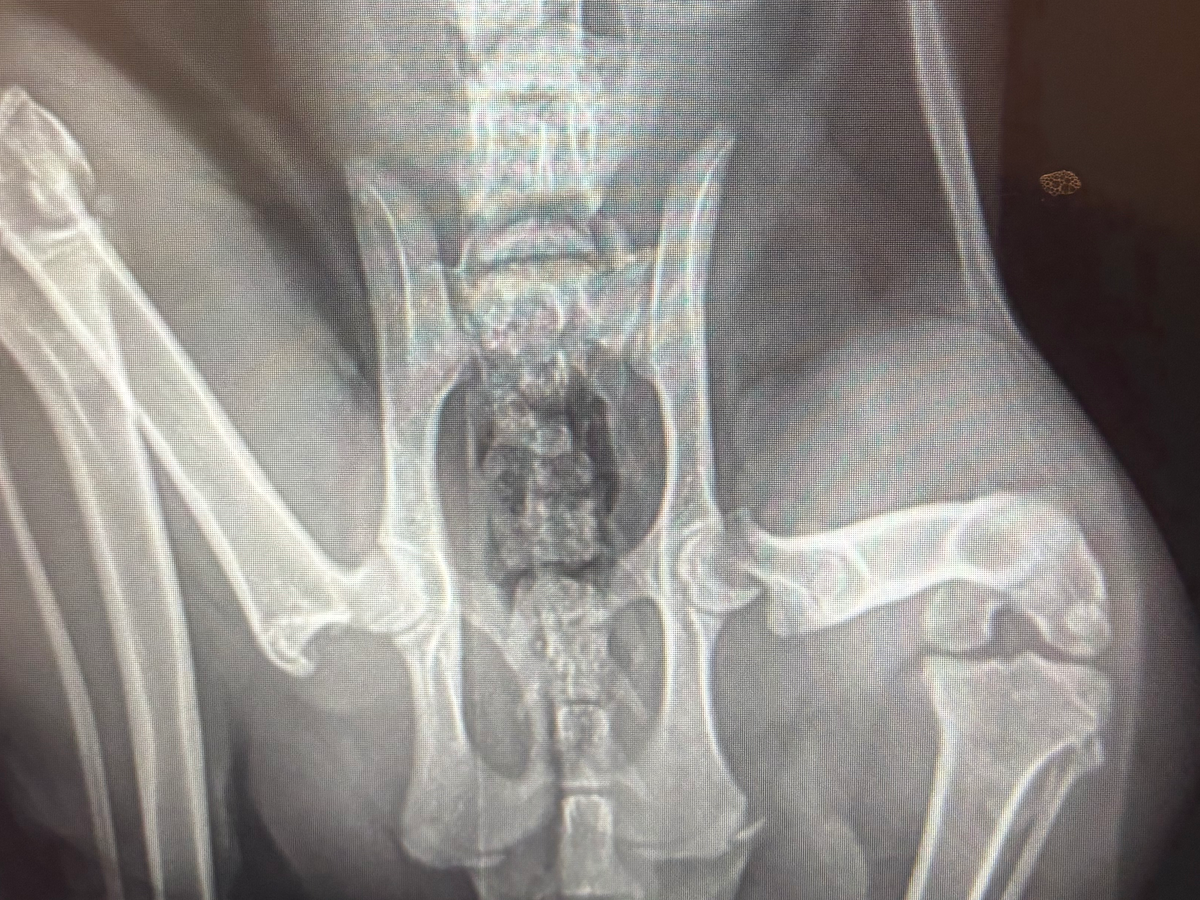

He was having some mobility issues, so we took an X-ray last night and found he needs FHO surgery on his left leg. This was a very unexpected expense that I was not prepared to take on, but this guy deserves a chance at a good life. He is so sweet and loves to cuddle, he eats well, and will have a good prognosis with surgery.